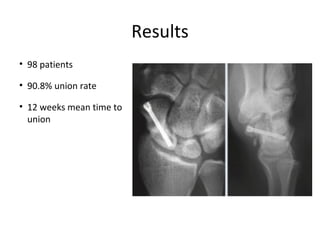

This presentation discusses various topics related to the wrist including static scapholunate ligament dissociation, dorsal ganglion cysts originating from the dorsal capsulolunate septum, treatment of scaphoid pseudarthrosis using a bone graft from the distal radius placed under the extensor tendons, and proximal pole scaphoid pseudarthrosis treated with capitolunate arthrodesis. It also thanks attendees and provides instructions for accessing the presentation online.